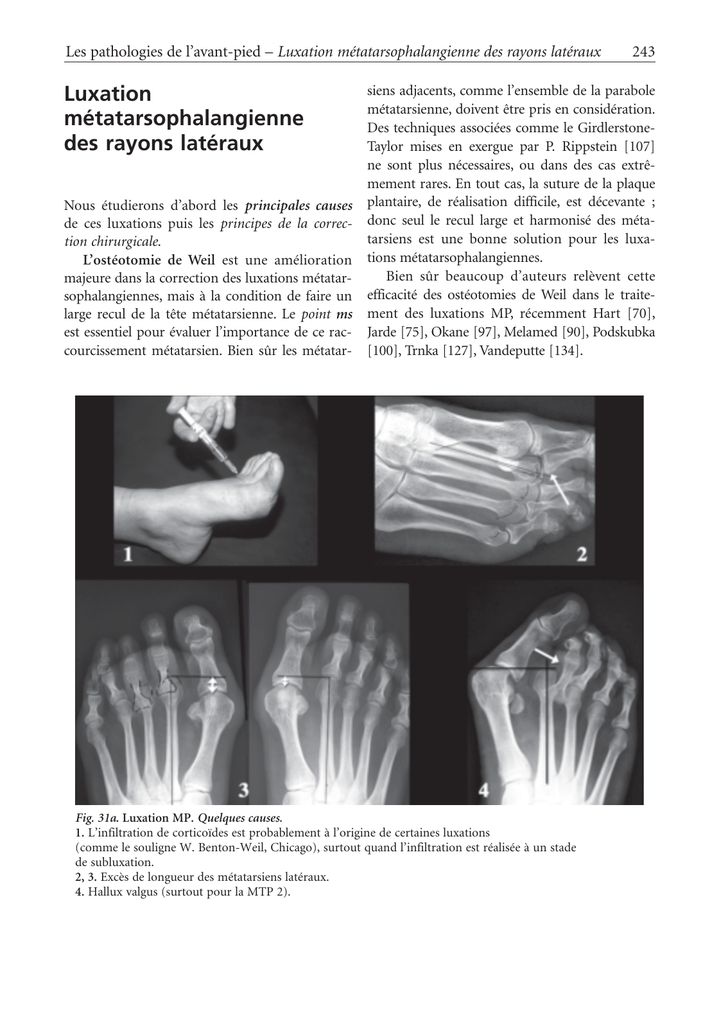

Fig. 31a. Luxation MP. Quelques causes.

1. L’infiltration de corticoïdes est probablement à l’origine de certaines luxations

(comme le souligne W. Benton-Weil, Chicago), surtout quand l’infiltration est réalisée à un stade

de subluxation.

2, 3. Excès de longueur des métatarsiens latéraux.

4. Hallux valgus (surtout pour la MTP 2).